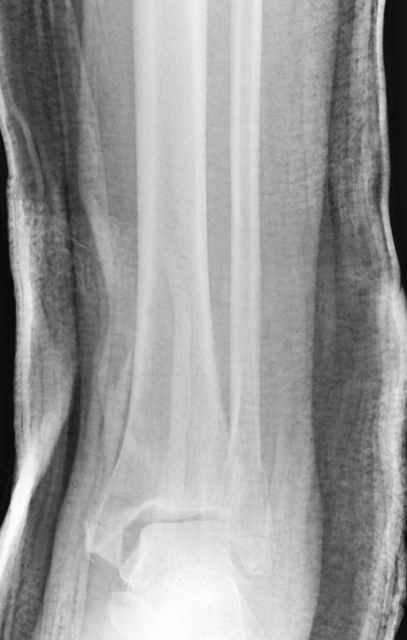

Dear all,40 y.o. man had sustained this terrible fracture falling from a motorbike.

Closed fracture.

We have put his limb in traction.

This is really Pilon Fx (C3.3; the high energy and the extent of distal tibia comminution are defining it).

This is a pilon fracture. I suggest fixation of the fibula with a one-third tubular plate and a joint spanning external fixator on the medial side as initial treatment. If the tibial articular surface cannot be reconstituted, the patient will require an arthrodesis.